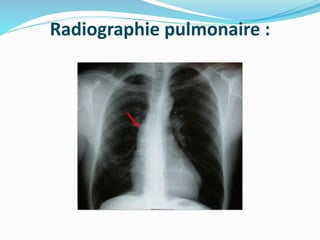

Radiographie pulmonaire :

- Cardiomégalie : débute aux dépens de l’arc inférieur gauche,

avec une pointe sous-diaphragmatique.

- Calcifications possibles au niveau de la valve aortique.

- Dilatation de la racine aortique : élargissement de l’arc

supérieur gauche, déroulement de la silhouette aortique, arc

moyen gauche concave.

- Signes d’insuffisance cardiaque : lignes B de Kerley,

redistribution vasculaire vers l’apex, opacités alvéolaires

périhilaires et hilifuges.

-Signe de "sonnette" à la radioscopie.